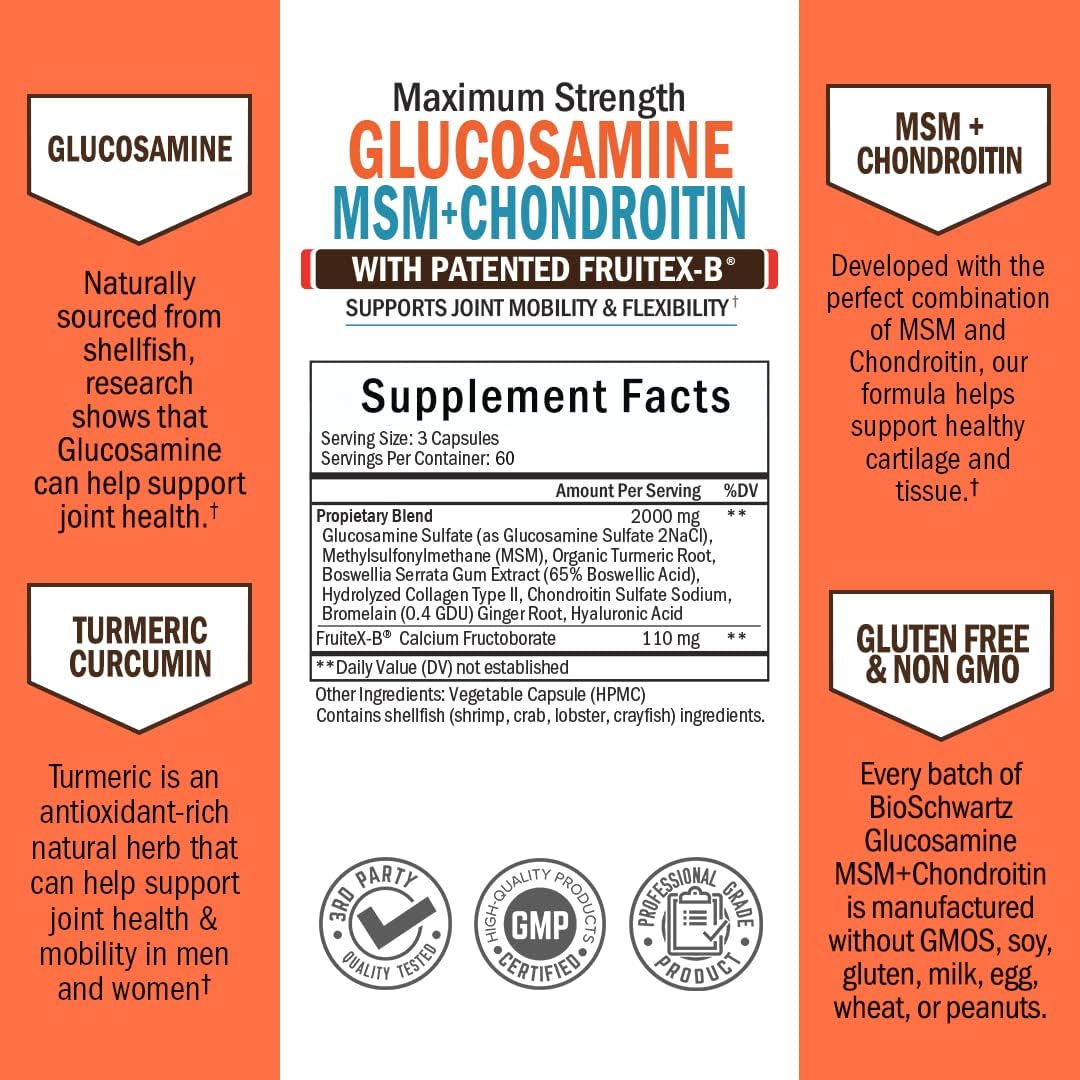

BioSchwartz Glucosamine MSM Chondroitin is formulated with a proprietary blend of 10 powerful ingredients, including Patented Fruitex-B, Boswellia Extract and Turmeric Curcumin to promote a healthy inflammatory response to easy discomfort and support mobility.†

This powerfully potent formula that helps to protect bones and provide the nutrients necessary to nurture healthy cartilage to maintain sound joint structure.†

We've combined Chondroitin Sulfate with Hyaluronic Acid and Hydrolyzed Collagen, two more components critical to proper joint lubrication and sustained mobility for maximum efficacy.†

BioSchwartz Glucosamine MSM Chondroitin is formulated with a proprietary blend of 10 powerful ingredients, including Patented Fruitex-B, Boswellia Extract and Turmeric Curcumin to promote a healthy inflammatory response to easy discomfort and support mobility.†

This powerfully potent formula that helps to protect bones and provide the nutrients necessary to nurture healthy cartilage to maintain sound joint structure.†

We've combined Chondroitin Sulfate with Hyaluronic Acid and Hydrolyzed Collagen, two more components critical to proper joint lubrication and sustained mobility for maximum efficacy.†